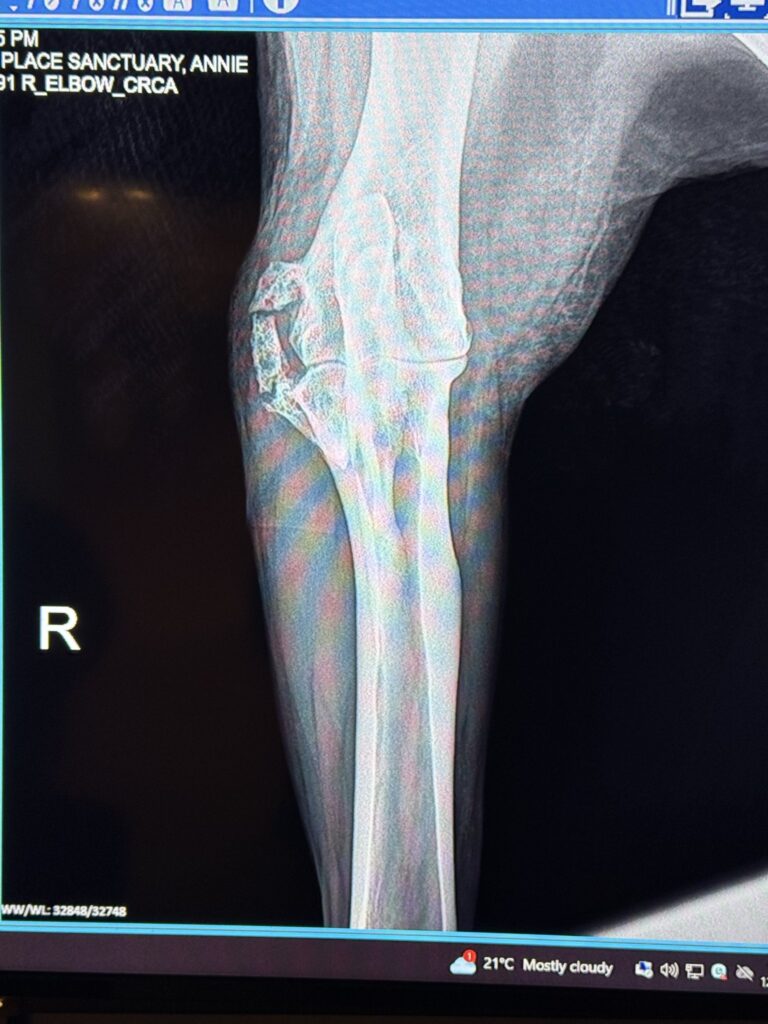

Annie then had X-rays and bloodwork done. X-rays showed arthritis in both of Annie’s front legs, which we already knew. However, the arthritis on her right side is actually worse than the left—even though it’s her left leg that’s been bothering her. As a result, arthritis was ruled out as the cause.

An X-ray image from another angle clearly showed the problem: Annie has a fracture in her ulna, just below the joint. There are visible signs that her body has been trying to heal itself for some time, which, again, isn’t surprising, as she’s been on stall rest due to her leg bothering her. Even though her body has been trying to heal, it’s very unlikely that this kinda of fracture will ever heal on its own.